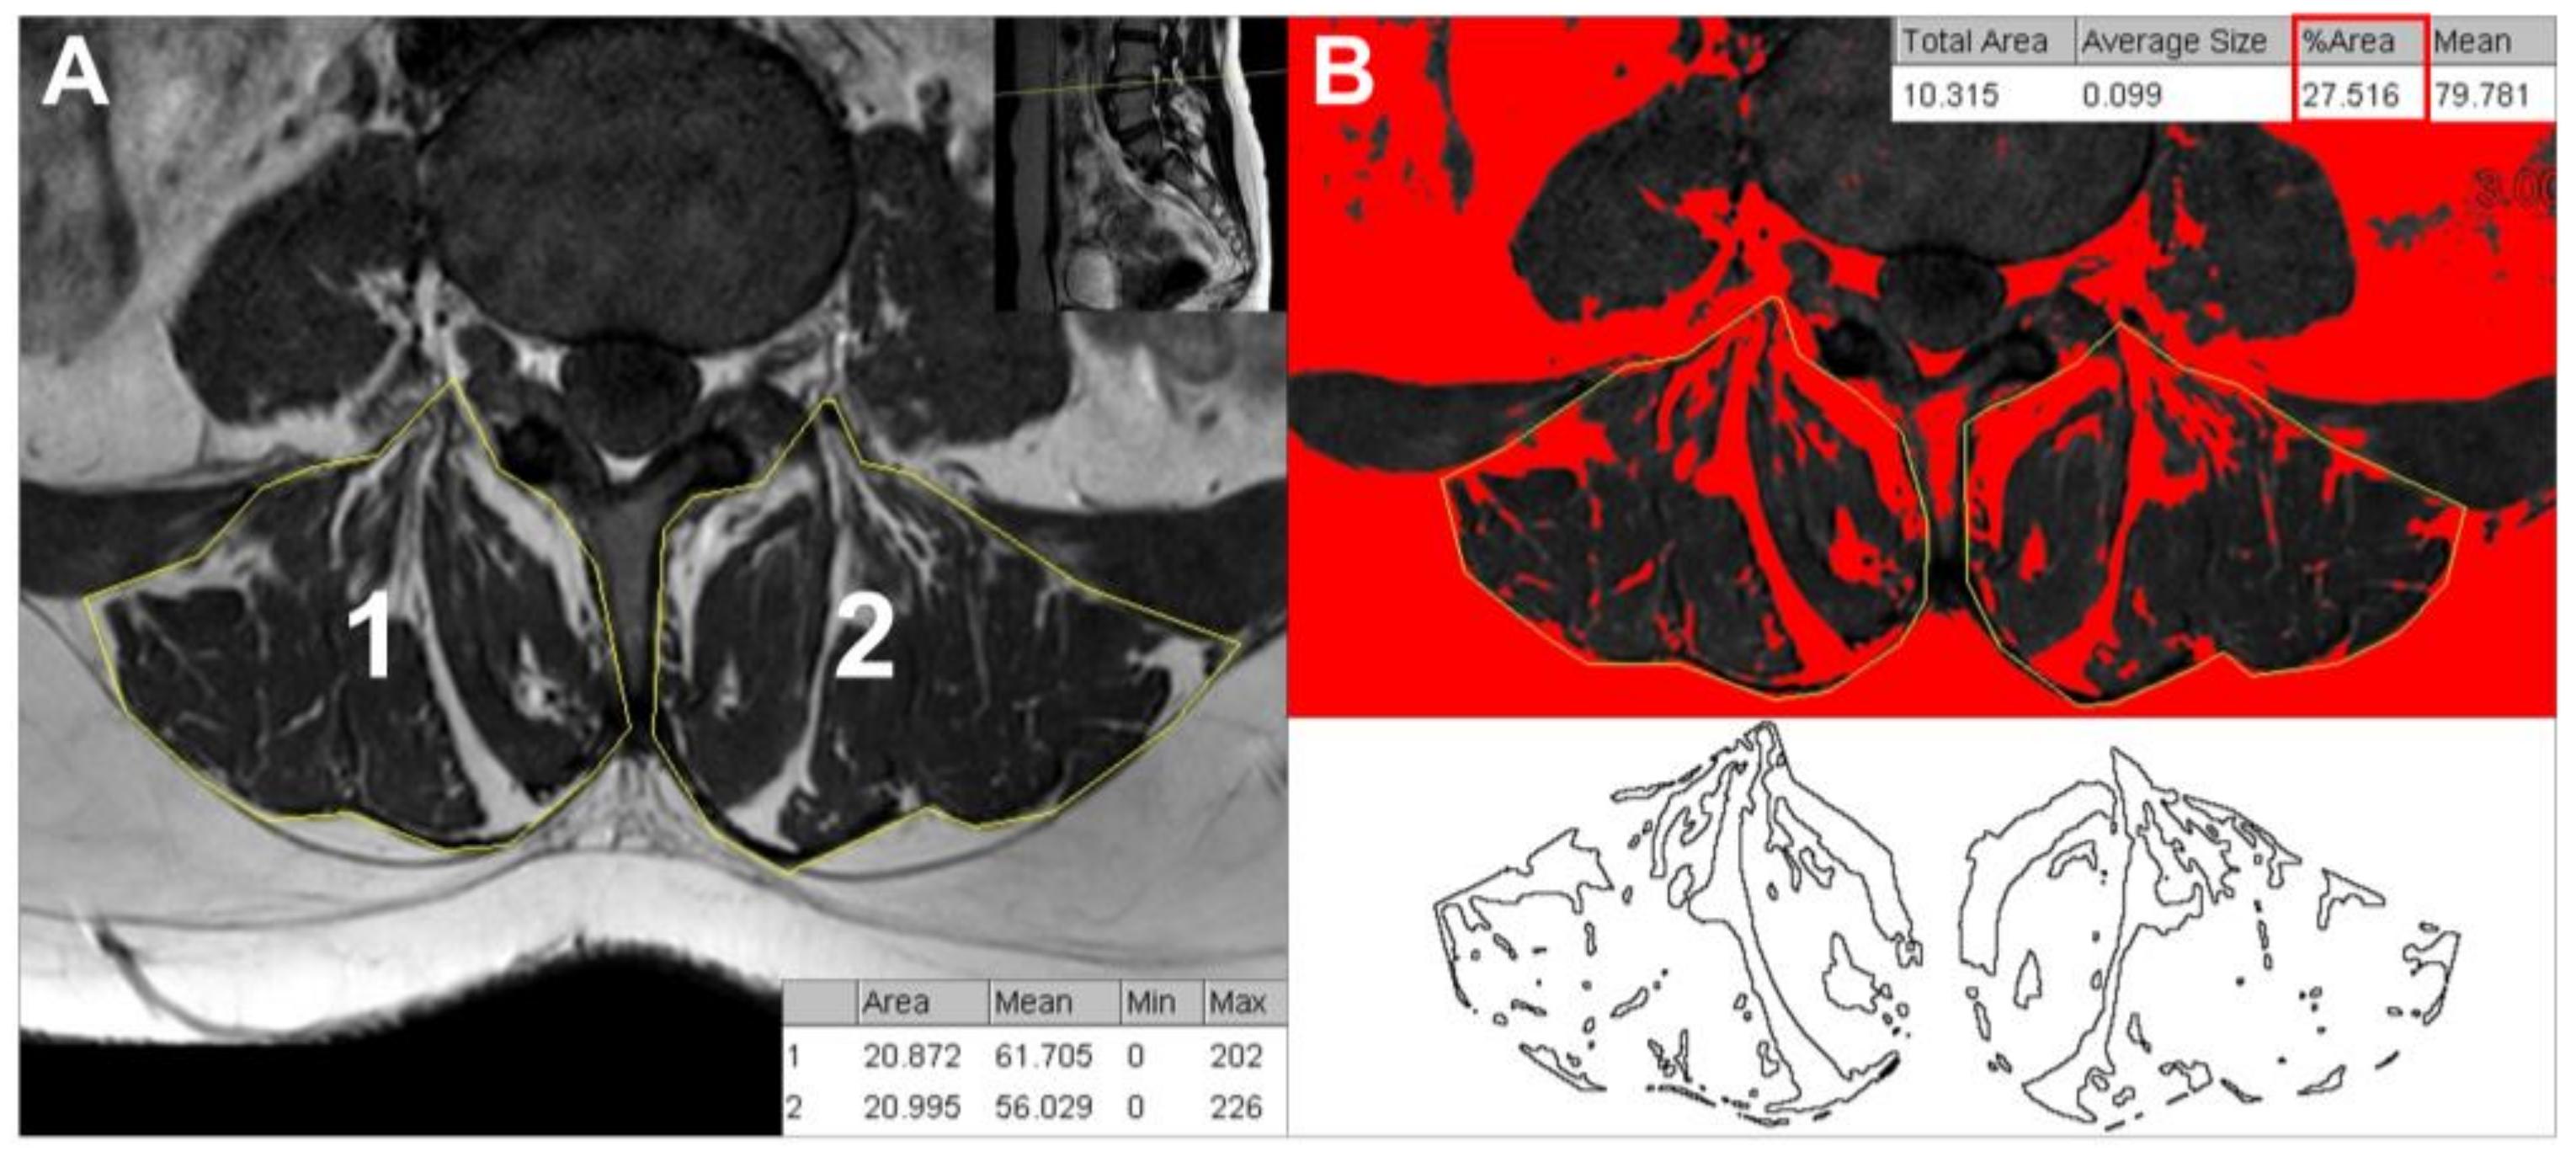

2.2. CSA and Fatty Infiltration Measures